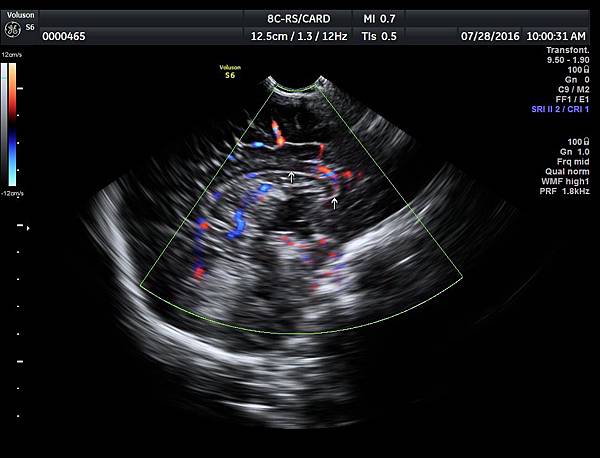

1. 矢狀切面(sagittal plane):駢胝體呈現類似三明治的中間黑色部分,上面一層薄薄白色的區域是callosum sulcus,打上flow可以看到pericallosum artery在駢胝體上面的周圍,pericallosum artery來源是前腦動脈,參考附圖 6~10,三明治下面白白的部分是和CSP做比較得到的,如果這一層長lipoma(附圖 5),CSP很可能看不到。

附上2016年7月28日我在診所幫一位一個半月的嬰兒照的腦部超音波,經由前囟門進入,駢胝體可以很容易的被完整看到,參考附圖15~16。